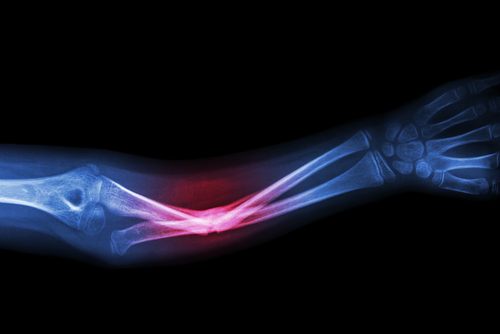

Biologiškai absorbuojamas klijai, vadinami „Bone-02“, tariamai sujungia kaulų fragmentus per kelias minutes, veikia drėgnose, krauju užpildytose chirurginėse srityse ir ištirpsta per kelis mėnesius. Ankstyvieji klinikiniai tyrimai, įskaitant riešo lūžius, rodo greitą fiksavimą ir matomą stiprumą, dėl kurio galima išvengti metalinių plokščių ir vėlesnio jų pašalinimo. Ši koncepcija remiasi austrių įkvėptais drėgnais klijais, tačiau paskelbti tyrimai, ilgalaikio saugumo duomenys ir reguliavimo leidimai tebėra riboti, todėl kyla praktinių ir mokslinių klausimų dėl platesnio taikymo.

Jų tikslas – fiksuoti lūžius, suformuojant greitai kietėjančią jungtį drėgnose, krauju užpildytose chirurginėse srityse, ir, kaip teigiama, pasiekiant tikslų fiksavimą per dvi ar tris minutes. Kūrėjai apibūdina klijų sukibimo gebą kaip viršijančią 181,4 kilogramus, o laboratoriniai ir bandomieji matavimai rodo, kad jų šlyties stipris yra apie 0,5 MPa, o gniuždymo stipris – apie 10 MPa.

Naujausiuose klinikiniuose pranešimuose ir ankstyvose bandymų ataskaitose tyrėjai aprašo daug žadančius, bet preliminarius austrių įkvėpto klijaus rezultatus: daugiau nei 150 pacientų buvo gydyti, vieno pjūvio riešo lūžio remontas, kuris pasiekė tikslų fiksavimą per maždaug tris minutes ir rentgenografinį gijimą per tris mėnesius, išmatuotos mechaninės savybės su šlyties stiprumu artimu 0,5 MPa ir gniuždymo stiprumu apie 10 MPa, ir deklaruotas bandymų stende arba klinikinis klijavimo pajėgumas, viršijantis 181 kg.

Palyginti su tradicinėmis plokštelėmis ir varžtais, austrių įkvėptas klijais yra žymiai greitesnis, minimaliai invazinis variantas, kuris sujungia fragmentus per kelias minutes ir leidžia išvengti įprasto metalinių detalių pašalinimo. Jis užtikrina stiprų greitą fiksavimą (didžiausia jėga >181 kg; šlyties ~0,5 MPa; gniuždymo ~10 MPa) ir vieną injekciją, kuri gali sutrumpinti operacijas ir sumažinti infekcijos riziką.